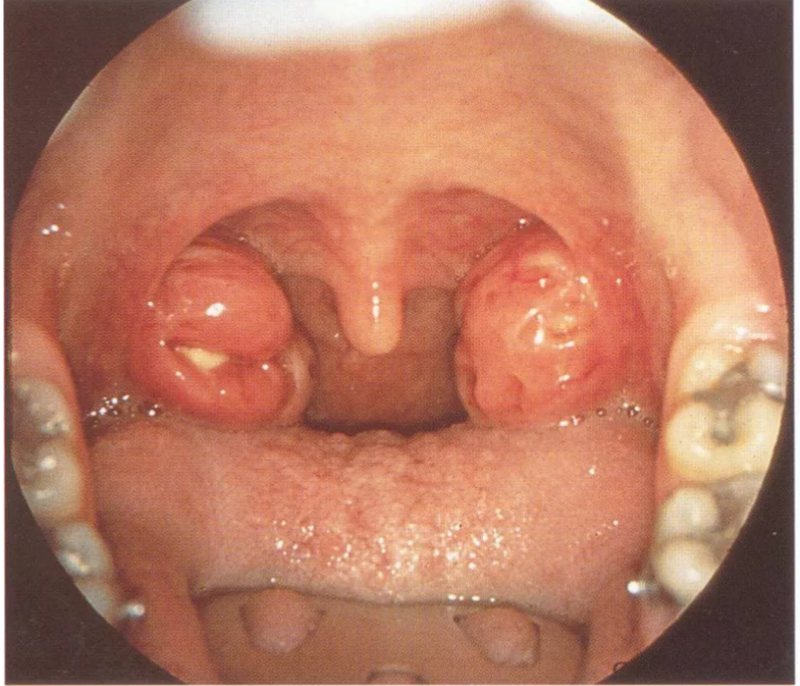

临床上遇到难缠的咽痛,除扁桃体炎以外,应警惕扁桃体周脓肿,早发现,早排脓。 1概 述 扁桃体周脓肿为扁桃体周围隙内的化脓性炎症,早期发生蜂窝织炎(称为扁桃体周围炎) 继之形成脓肿。多见于青壮年,平均年龄20-35岁,儿童和老人少见,国外报道年龄最小患者为4个月婴儿。 本病多单侧发病,两侧同时发病者极少。按其发生部位,临床上可分为前上型和后上型两种。前者脓肿位于扁桃体上极与舌腭弓之间,此型最常见;后者位于扁桃体与咽腭弓之间,较少见。 2临床表现 在扁桃体急性发炎3~4天后,发热仍持续不退或又加重,体温上升达39℃以上,咽痛加剧,吞咽时尤甚。常限于患侧,可放射至同侧耳部及牙齿。 病情严重时患者头偏向患侧,不易转动(假性僵直)。讲话时似口中含物不清,张口受限,口内有多量粘稠唾液沿口角外流。同侧下颌角淋巴结常肿大。身体衰弱。 3体 征 患者呈急性病容,表情痛苦,因剧烈咽痛和张口困难,检查常不合作。 早期周围炎时,可见一侧舌腭弓显著充血。若局部明显隆起,甚至张口困难,提示脓肿已形成。 前上型者,患侧腭舌弓及软腭红肿突出,悬雍垂水肿,偏向对侧,舌腭弓上方隆起,扁桃体被遮盖且推向内下方。病程7~10天者,有的脓肿可自行破溃排脓。 属后上型者,患侧咽腭弓红肿呈圆柱状,扁桃体被推向前下方,软腭与悬雍垂可无水肿,常无张口困难。但是,炎症可向下扩散至喉咽部及喉入口等处,可引起喉水肿等并发症。 4诊 断 根据上述临床表现及检查,诊断不难。 咽痛逾4-5天,局部隆起明显及剧烈咽痛,即可判定脓肿已形成,穿刺抽脓可确定诊断。 超声诊断显示扁桃体周脓肿的敏感度为90.9%,其鉴别扁桃体周围炎和扁桃体周脓肿的准确率可达88.9%,特异性为80%。扁桃体增大或均匀的脓肿可通过口外超声检查证实,但当扁桃体周脓肿为不均匀的囊腔时,经口内超声检查准确率更高。 5鉴别诊断 扁桃体脓肿:为扁桃体本身的脓肿,可在扁桃体内抽出脓液,患者扁桃体肿大,扁桃体上隐窝中可见脓液流出,患者多无张口困难。 扁桃体恶性肿瘤:一般无发热,一侧扁桃体迅速增大或扁桃体肿大而有溃疡,均应考虑肿瘤的可能,活检可确诊。 脓性颌下炎:为口底的急性炎症,形成弥漫性蜂窝织炎。在口底及颏下有痛性硬块,舌被抬高。压舌或伸舌时感到疼痛和困难,张口受限但非牙关紧闭。感染可扩散至喉部,引起呼吸困难。软腭及舌腭弓无充血隆起。 6治 疗 经及时合理的治疗,病情可迅速控制,预后良好。 1. 脓肿形成前的处理: 其治疗与急性扁桃体炎相同。给予足量的抗生素类药物及适量的类固醇激素,并给予输液、对症治疗。 2. 脓肿形成后的处理 (1)穿刺抽脓: 可明确脓肿是否形成及脓腔部位。2%丁卡因表面麻醉后,用16~18号粗针头于脓肿最隆起处刺入;穿刺时,应注意方位,不可刺入太深,以免误伤咽旁隙内大血管,针进入脓腔,即有脓液抽出。 (2)切开排脓: 前上型者可在穿刺获脓处、或在选择最隆起或最软化处,常规定位是:从悬雍椎根部作一假想的水平线,从腭舌弓游离缘下端(与舌根交界处)作一假想的垂直线。二线交点稍外即为适宜切口之处,切开粘膜及浅层组织后(不宜过深,避免损伤大血管)用长弯血管钳向后外方顺肌纤维走向撑开软组织,直达脓腔,充分排脓。术后不置引流。对后上型者则在腭咽弓处切开排脓,次日复查,必要时可再次分开排脓。 (3)施行扁桃体切除术: 适宜病程较长,多次切开排脓仍未治愈者。 患侧扁桃体切除后,具有排脓彻底,恢复快,且无复发的优点。术后疼痛较轻,发生出血、脓毒血症或其他并发症者极少,比缓解期施行手术有明显的优越性。 缺点是张口受限,操作不便。l3.脓肿消退后的处理:应在脓肿消退2周后,将扁桃体切除,以预防复发。

扁桃体周围脓肿